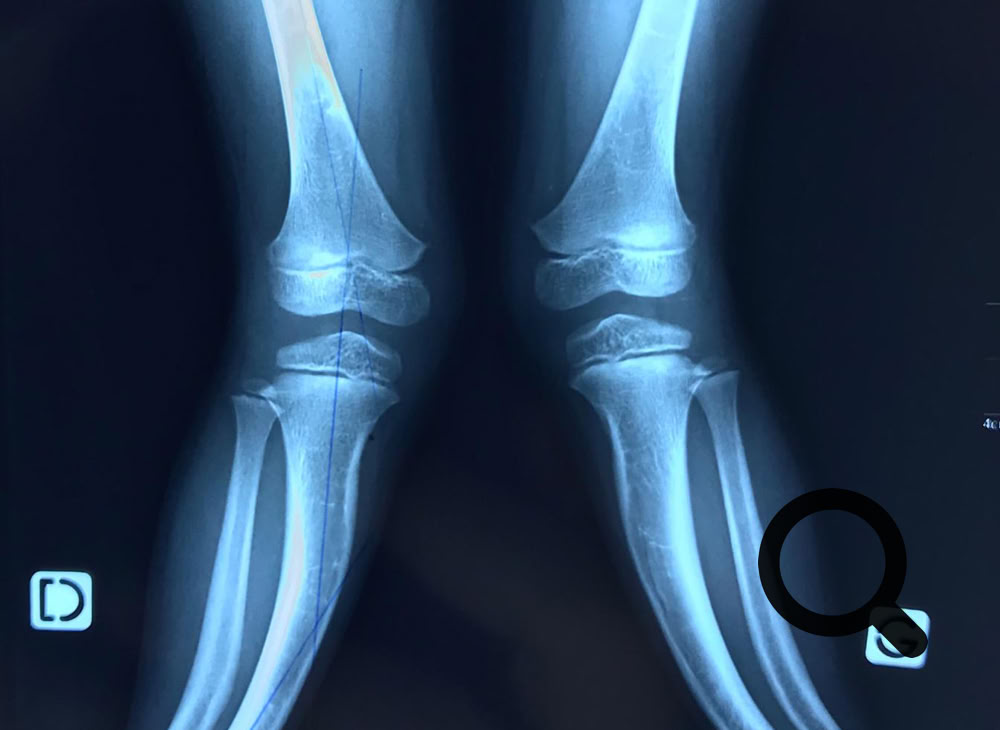

En esta ocasión hemos  tenido más cirugías de perfil pediátrico que en otras ocasiones, desde una amputación de miembro superior a una niña a la que no se pudo salvar su brazo hasta grandes deformidades e infecciones

Las cirugías han sido importantes para poder conseguir realizar todas esas correcciones y la evolución de los pacientes  en el post-operatorio inmediato ha sido satisfactoria.